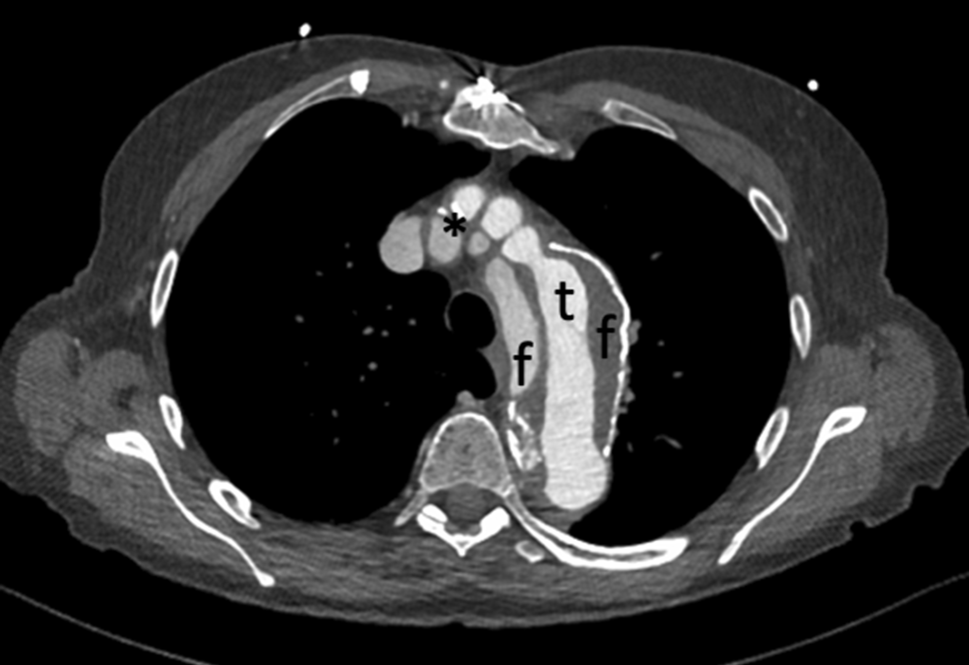

A computed tomography angiogram (CT-A) scan showed chronic residual dissection of the aortic root between the sinotubular junction/sinus of valsalva (Fig. 1) and the proximal end of the aortic prosthesis, which continued beyond the aortic arch (Fig. 2) into the descending aorta and iliofemoral vessels. It also showed partially dissected supraaortal branches and a partially thrombosed false lumen. Total diameter of the aortic arch was 4.5 cm, with true lumen diameter of 1.5 cm.

Fig. 1

Aortic arch with dissection (t true lumen, f false lumen with partial thrombosis, asterisk dissected supraaortal branches)